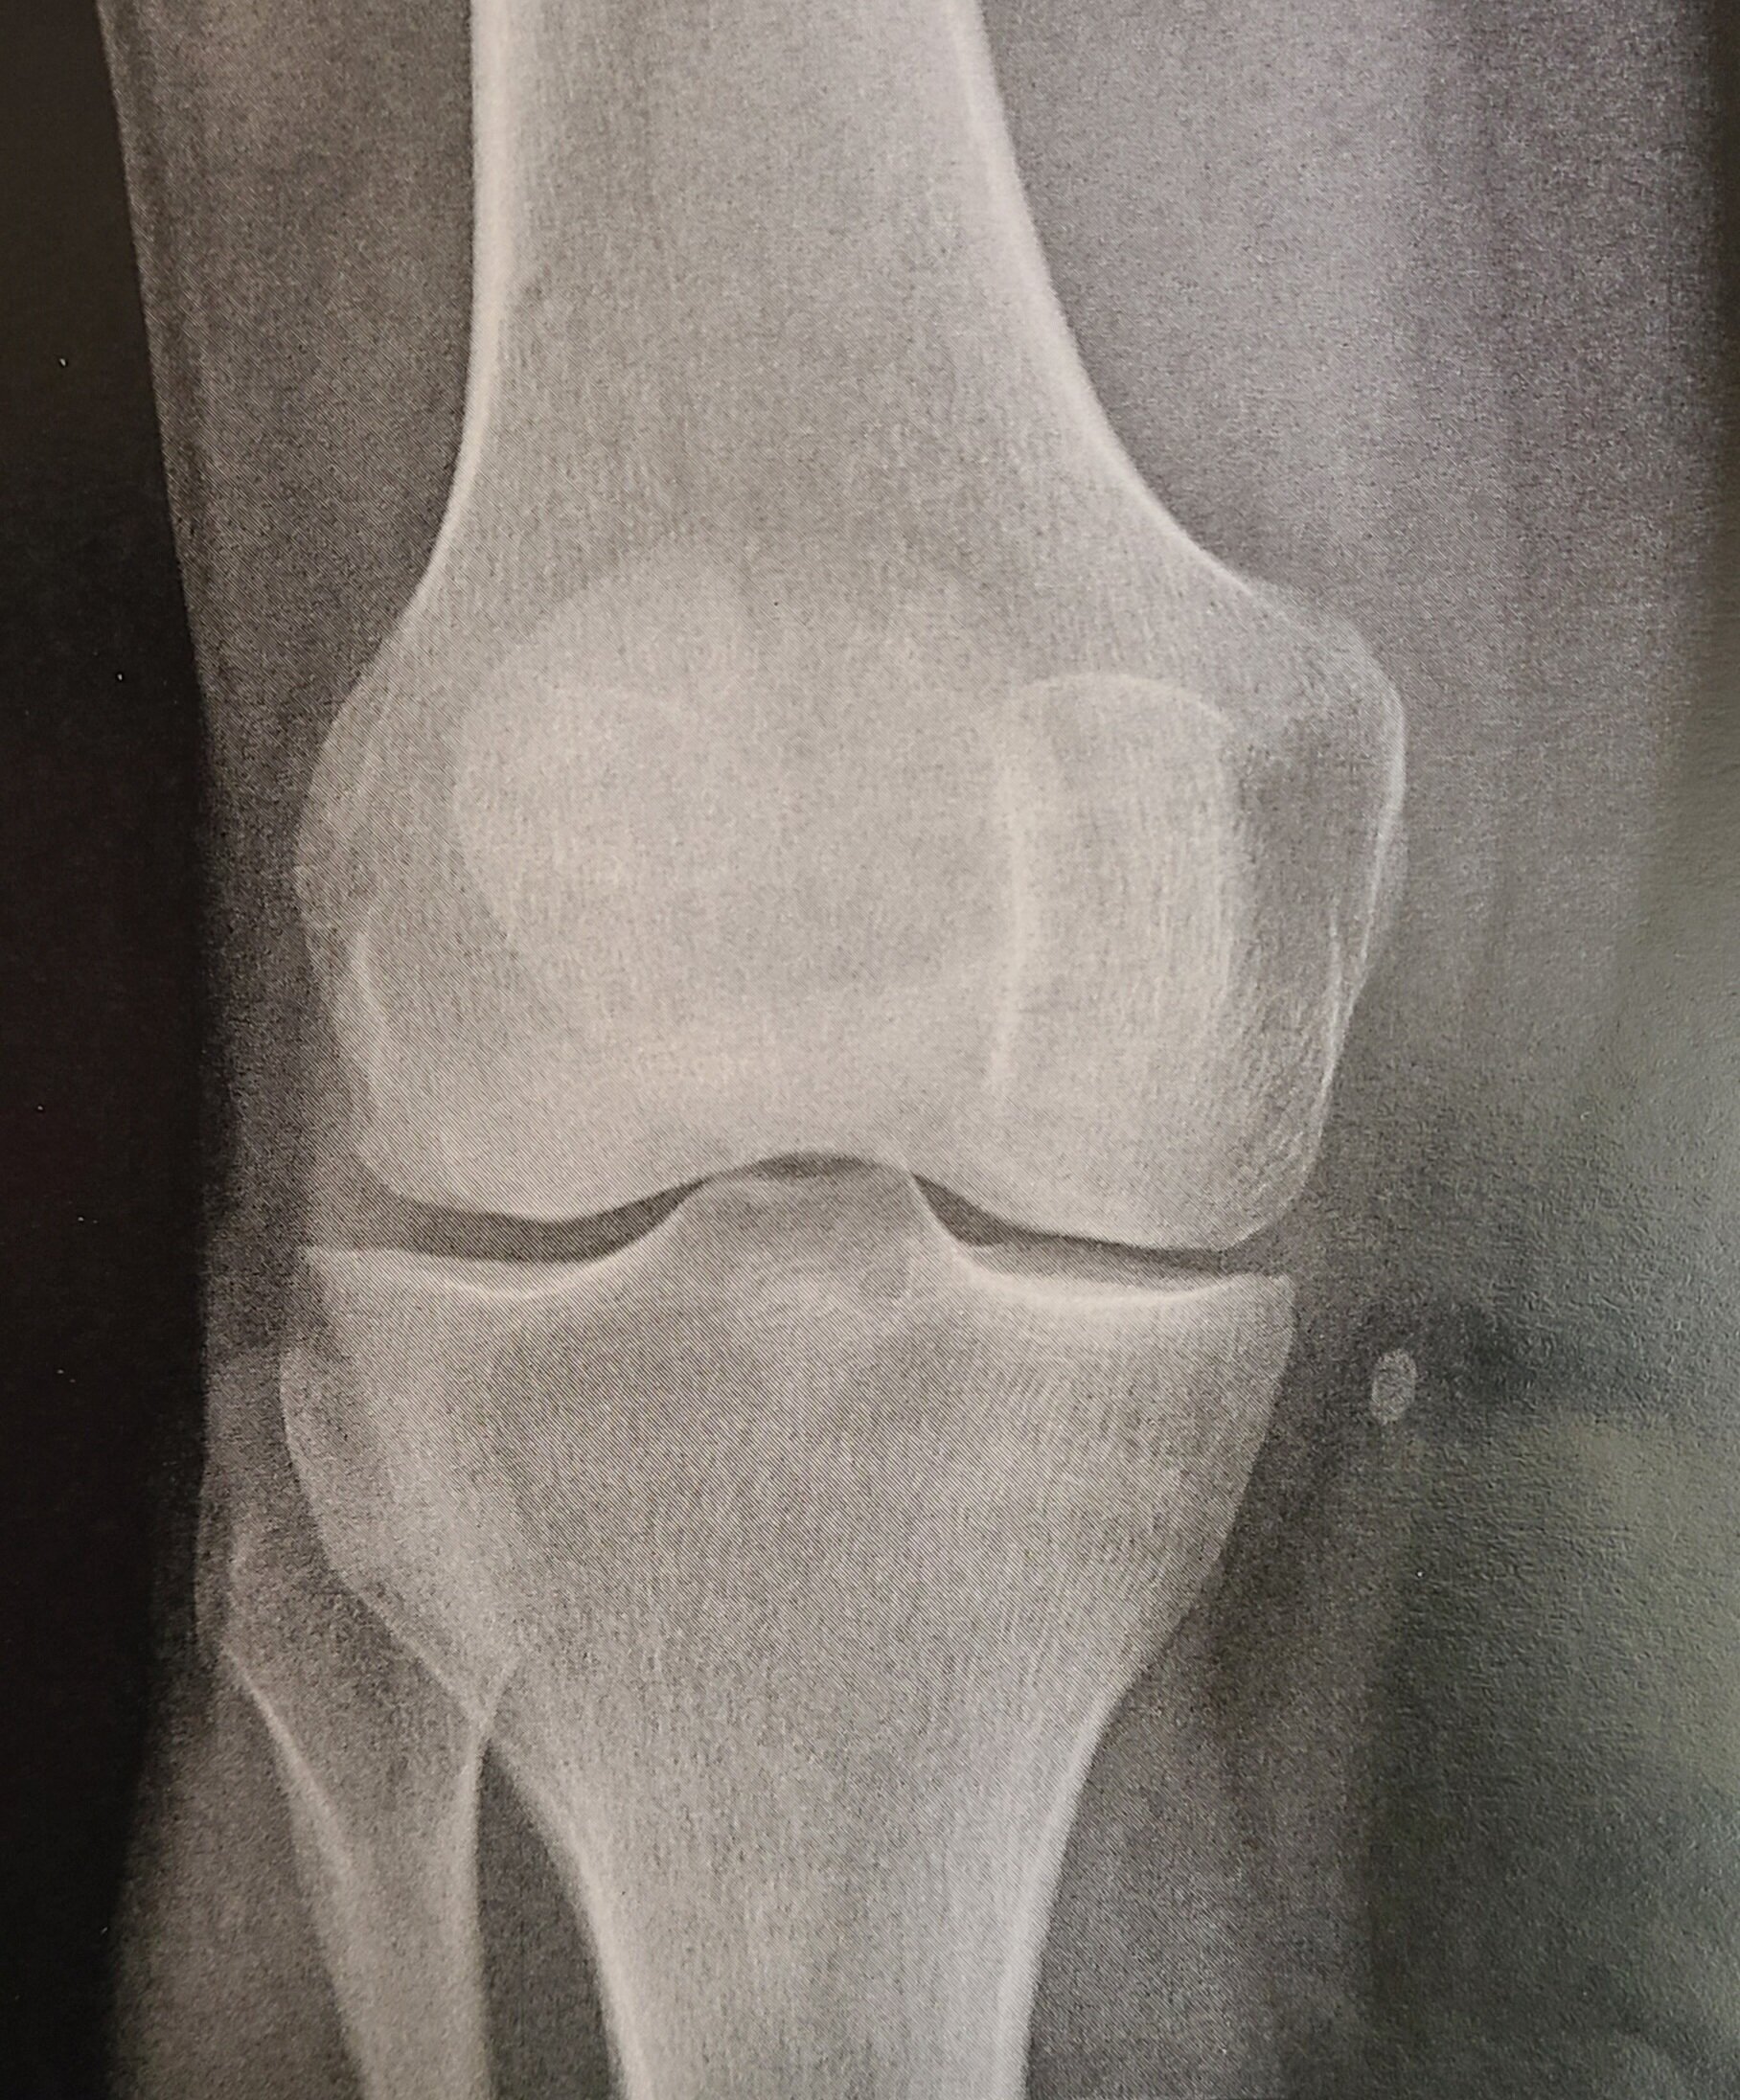

Station ECOS : Vous êtes interne de rhumatologie et une femme de 47 ans sans ATCD notables vous est adressée par son médecin traitant pour douleur mécanique chronique du genou droit. La radiographie retrouve un épanchement articulaire du même côté. L'examen clinique ne retrouve rien à part une masse en regard du tibia, indurée, mobile par rapport au plan profond, indolore, de petite taille. Quelles sont les étiologies les plus probables ?![]()